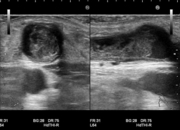

石灰化画像

吻合部画像

・吻合部の観察

吻合形態や、石灰化の有無、狭窄等を観察しています。